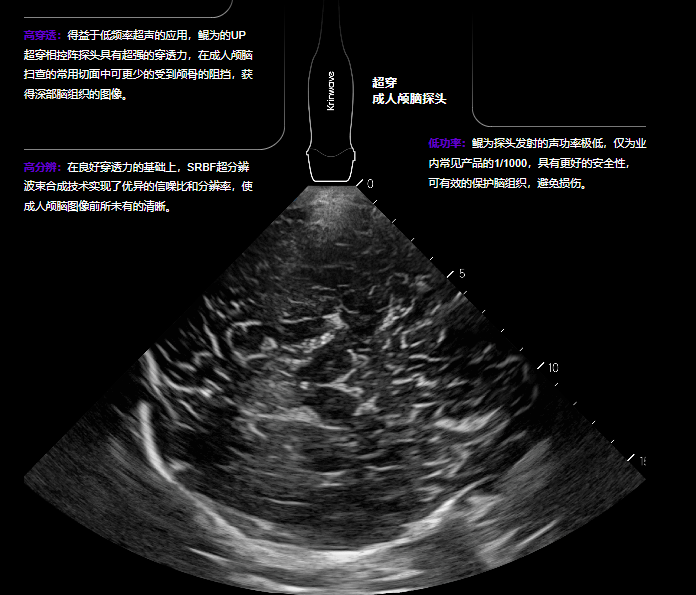

据介绍,鲲为独创的kOS成像平台,运用独特的EP全模态平面波、SRBF超分辨波束合成以及UP超穿探头,依托于强大的GPU处理能力,在业内首次打破了空间分辨力、时间分辨力和穿透力三大参数的制约关系,实现了超声影像技术的突破性革命。

其宣传物料显示,鲲为UP超穿探头穿透深度在中科院标准体模下探测深度达40CM,成像速度>5000帧/秒。

在具体应用方面,鲲为的SRUS超分辨成像在为传统的腹部/妇产/浅表等成像带来优异图像价值的同时,还能为尚处超声盲区的颅脑方面发挥了其独特的临床价值,开启颅脑超声时代。

图片

这一重大突破在于,当前成人颅脑超声技术主要局限于简单观测颅内血管,对颅内结构的显示几乎空白。随着老龄化社会的到来,心脑血管疾病成为人类健康的重大威胁。当前,颅脑检查主要依赖CT与磁共振成像,但这些检查不仅费用高昂,还需长时间等待,且成像过程繁琐,无法像超声成像那样在床边轻松快捷地进行。展望未来,颅脑超声技术潜力巨大,前景无限。